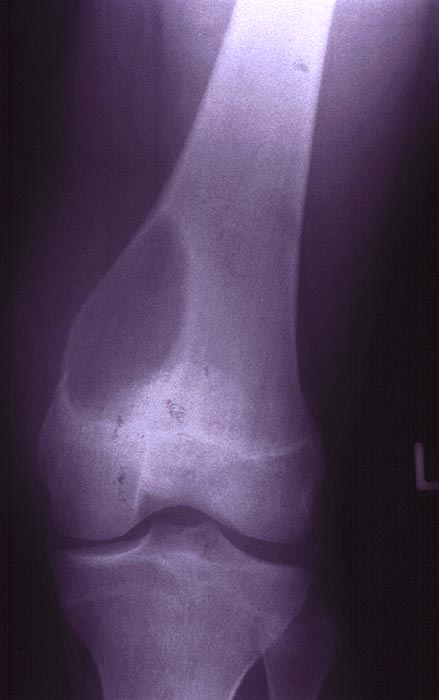

Radiologisch erkennt man in der distalen linken Femurmetaphyse medial eine exzentrisch gelegene Osteolysezone, die mediodorsal zu einer schalenartigen Ausbeulung des Knochens mit Bildung einer Neokortikalis geführt hat. Besonders nach dorsal ist die Neokortikalis sehr dünn.